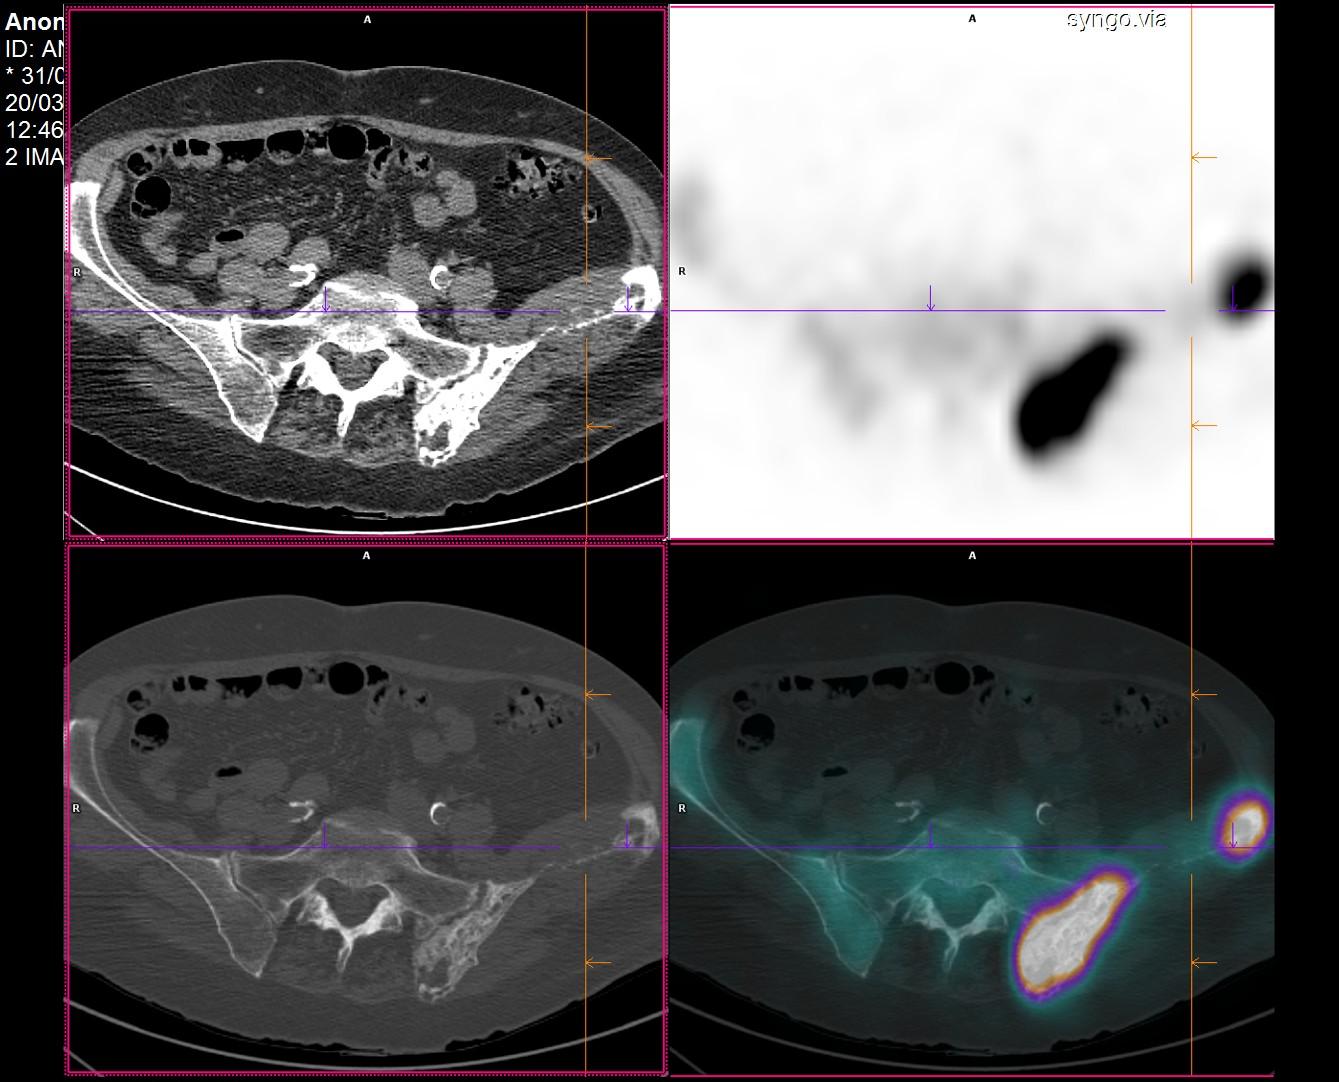

Bilan d’extension d’une néoplasie du sein découverte sur fracture pathologique du fémur gauche.

Anatomo-pathologie de la lésion osseuse fémorale : carcinome canalaire infiltrant RE+,RP- et HER2-.

Plusieurs lésions ostéolytiques peu voire non fixantes du pubis gauche,des ailes iliaques gauche et droite,de L4 (avec fracture pathologique) et de L5 correspondant à des lésions secondaires.

Hyperfixation intense et diffuse de l’hémi-bassin gauche associée à un aspect remanié de la trame osseuse avec dédifférenciation cortico-trabéculaire et épaississement des corticales,correspondant à une atteinte pagétique.

Hyperfixation du 1/3 inférieur de la diaphyse fémorale gauche correspondant à la fracture sur os pathologique

Métastases osseuses lytiques d’une néoplasie mammaire.

Maladie de Paget de l’hémi-bassin gauche.